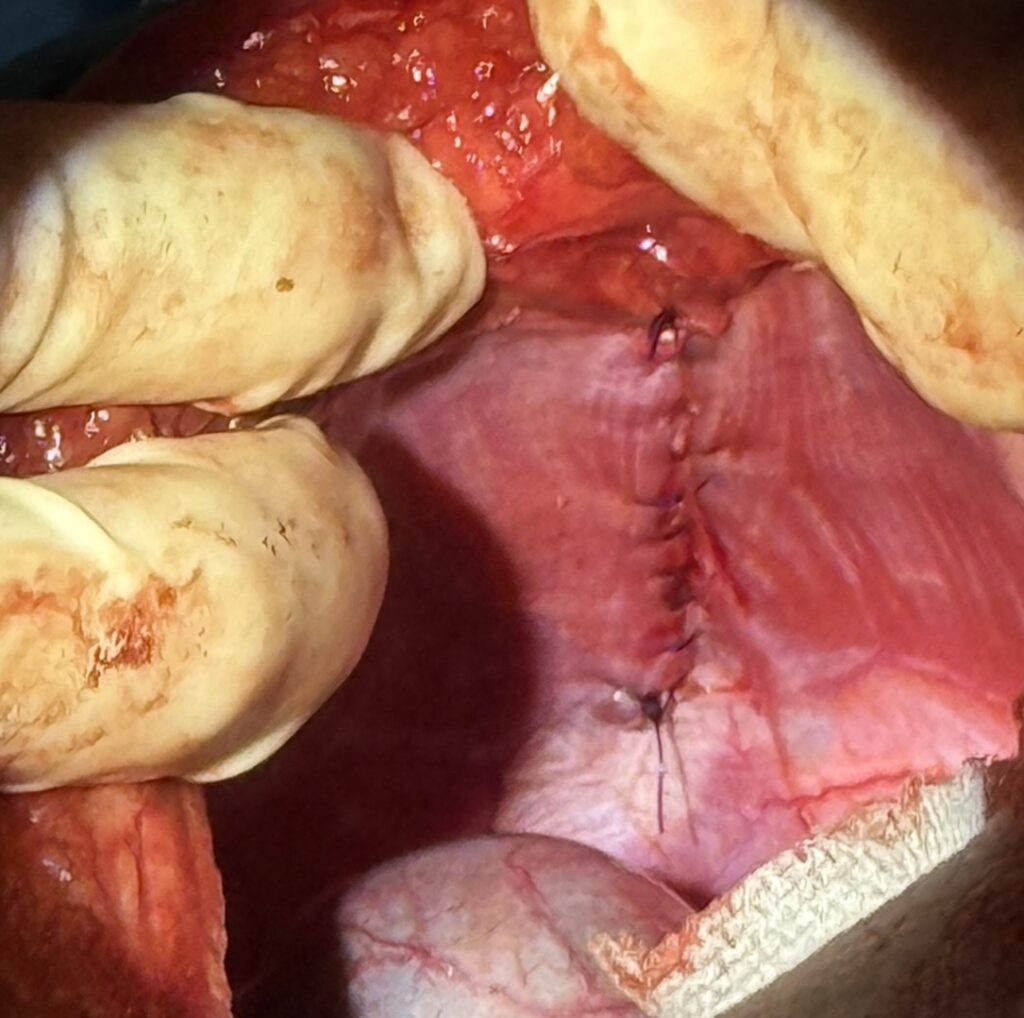

横隔膜内に開いている穴を確認し、慎重に肝臓を整復していきます。

臓器を整復した後は、横隔膜の穴を縫合していきます。 今回は癒着などもほとんどない状態でしたので、比較的侵襲少なく処置を終えることができました。

組織の癒着や胸水(心嚢水)貯留がある場合など、胸膜炎が激しい場合はこの後胸腔チューブを設置して術後管理をおこなっていきます。(今回は使用しませんでした)

術後は3日ほど入院して安静にしてもらい、元気に退院していきました。